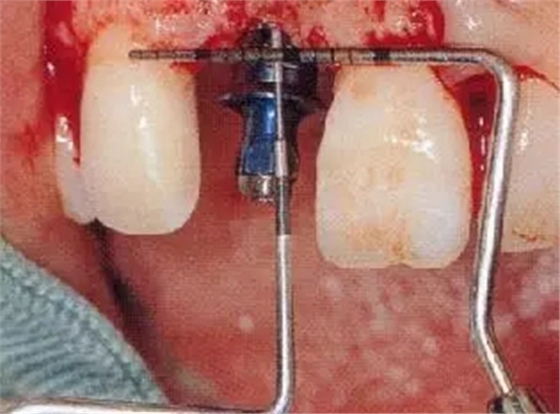

▲圖44-7,8

7個月后,牙齦組織的愈合狀態(tài)。

圖44-9~11 種植體植入時的狀態(tài)。將種植體邊緣植入低于兩鄰牙的牙齦線連線3mm的位置。頰舌方向則位于距唇側(cè)CEJ1mm的位置。